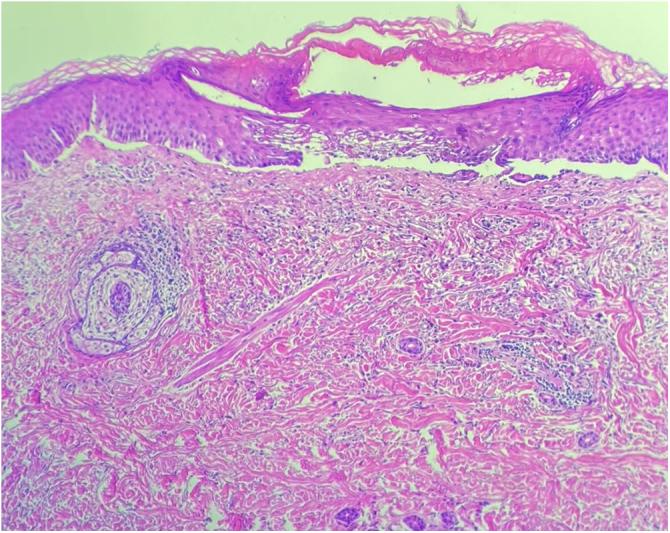

Bullous pemphigoid successfully treated with dupilumab.

An Bras Dermatol. 2024 Sep-Oct;99(5):778-780. doi: 10.1016/j.abd.2023.08.017. Epub 2024 Jun 13.